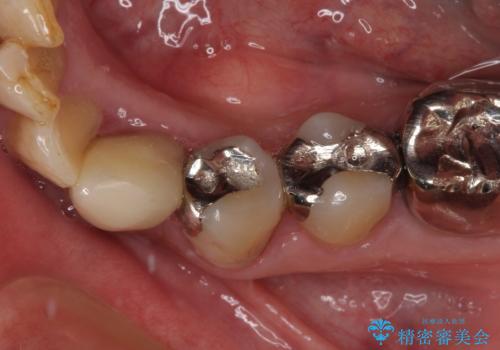

- クラウンがもげてしまった歯が抜歯と言われたとのことで来院された患者様です。

根管治療がされた歯であり、唇側に転位していたため、力がかかったことでクラウンが外れてしまったと判断されました。

麻酔下で歯肉を開いて診察をしたところ、唇側の歯肉縁下に深く歯が欠けている状態でした。